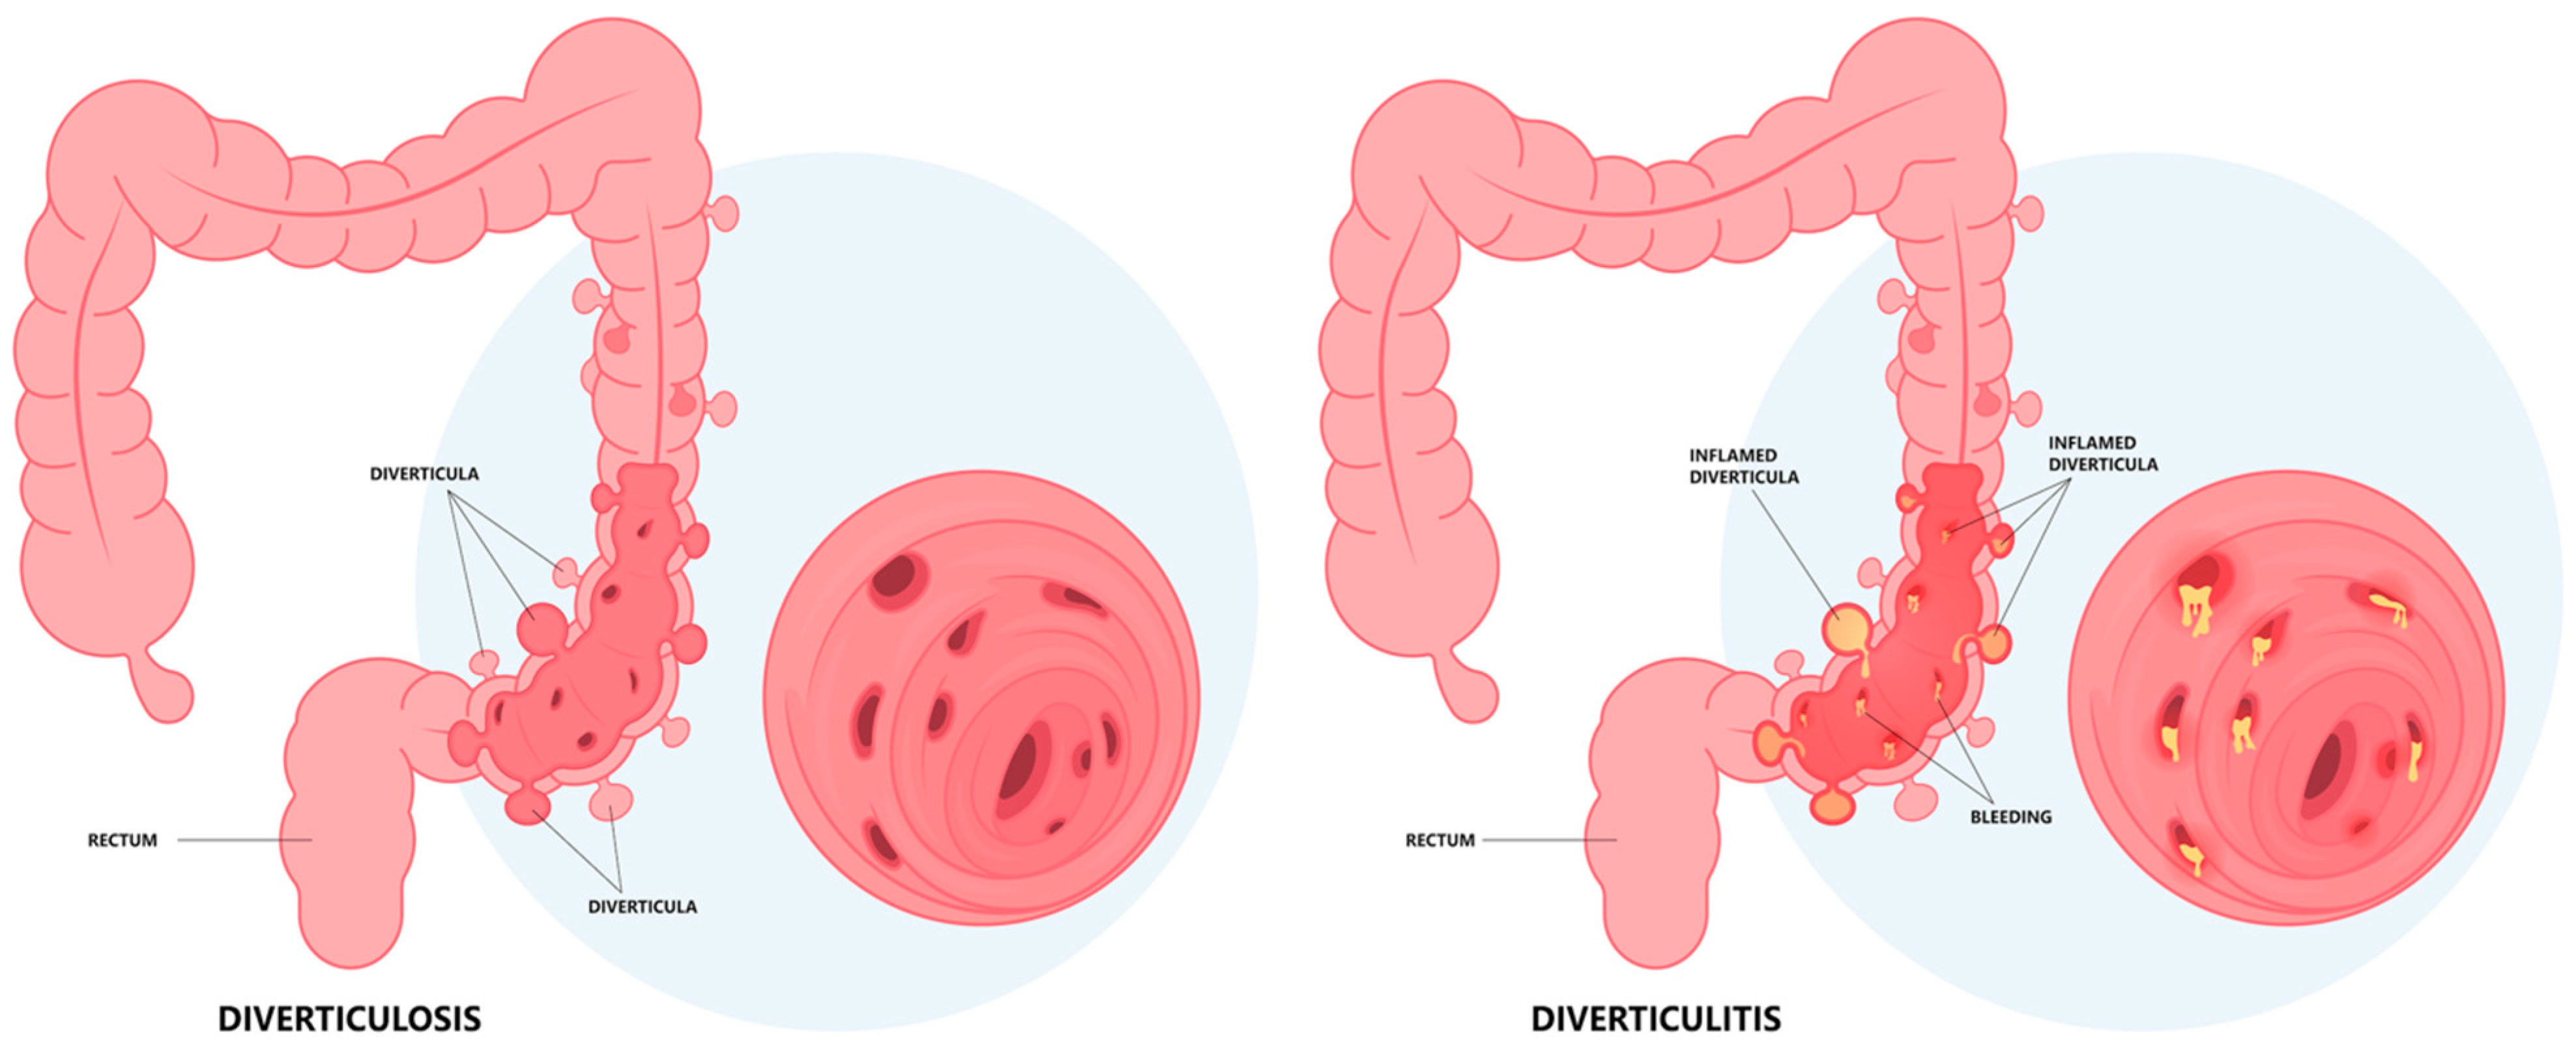

1.2. Pathogenesis

1.3. Diagnosis: Clinical Findings, Laboratory, Imaging, and Endoscopy